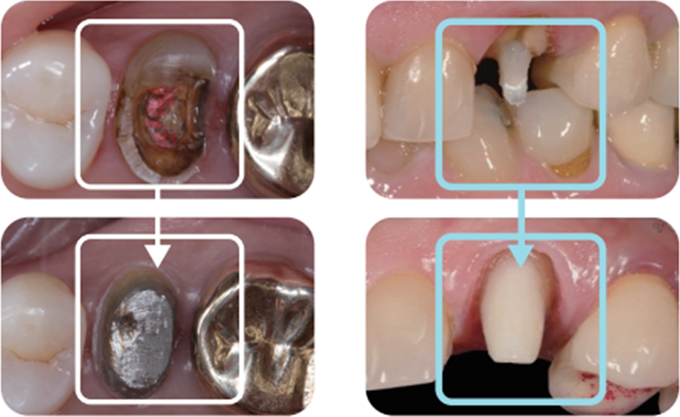

신경치료 후 남아있는 치질이 너무 짧거나 부족한 경우

크라운을 씌우기 전 치아안쪽에 기둥을 세우고 보강해주는 과정이 필요합니다.

포스트의 종류는 두가지가 있는데 사진은 기공소에서 맞춤형으로 제작된 포스트입니다.